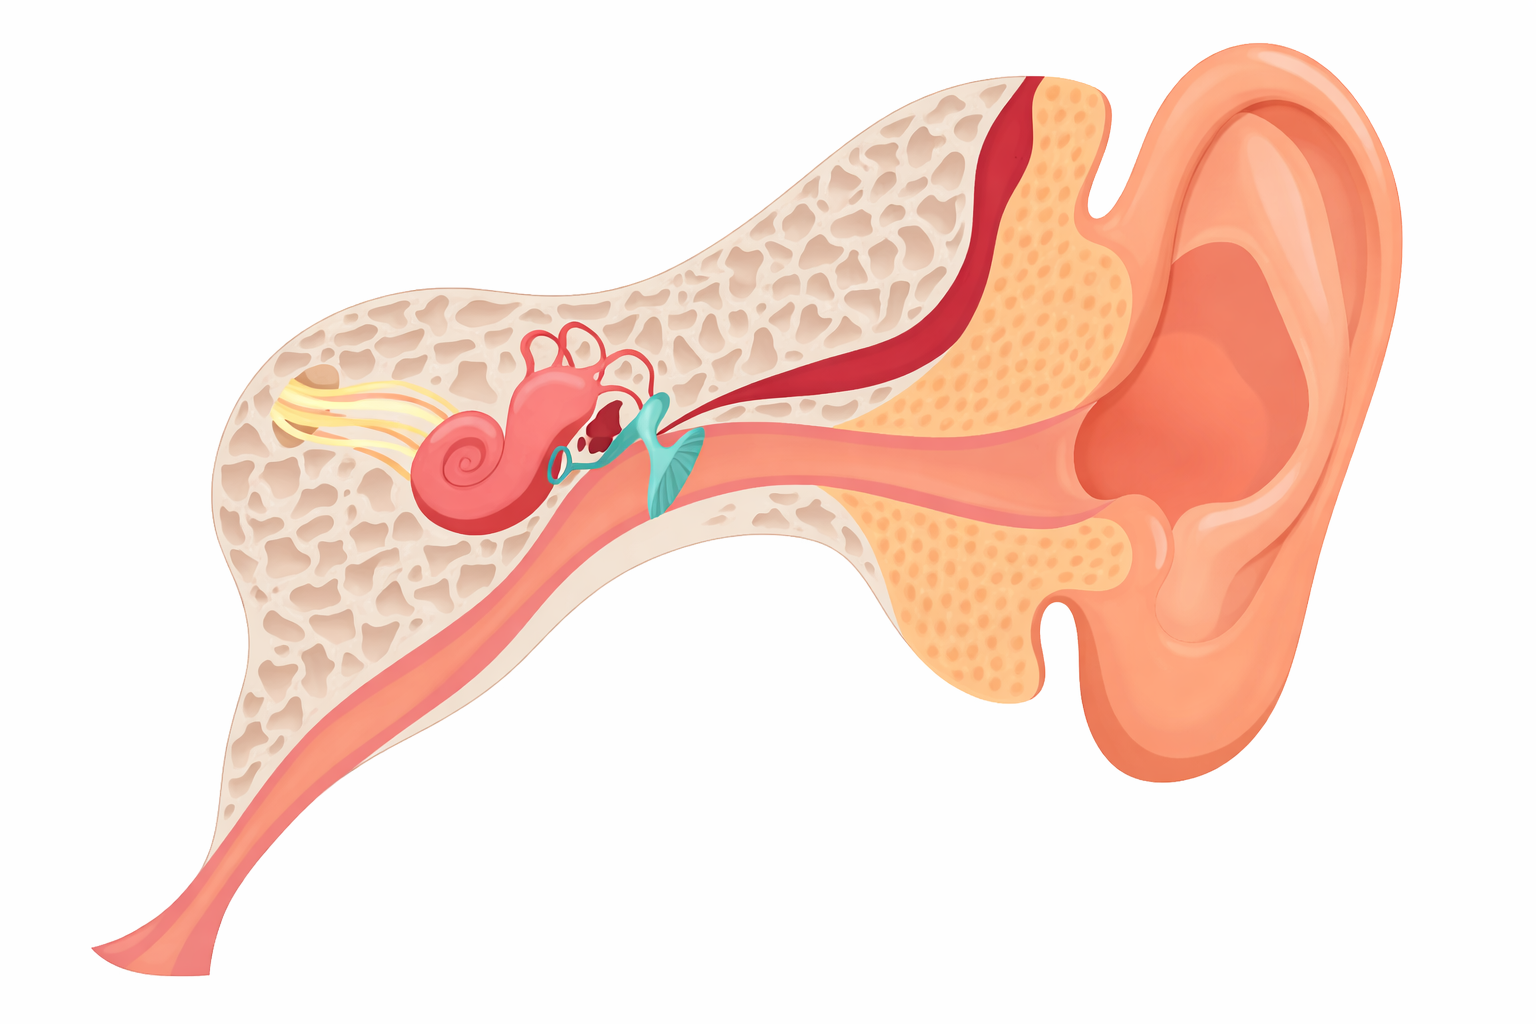

Eustachian Tube Dysfunction (ETD) is when the tube connecting the middle ear to the nose gets blocked or doesn’t function properly, causing ear pressure, discomfort, muffled hearing, and sometimes pain or dizziness. At Meraki ENT Hospital ETD is diagnosed and treated using advanced methods, including medications, nasal sprays, minor procedures, and exercises. Patients from Raidurg, HITEC City, Yousufguda, and Srinagar Colony, Hyderabad can access expert care.

ETD occurs when the Eustachian tube is blocked or not working properly, affecting ear pressure balance.

Symptoms include ear fullness, pressure, muffled hearing, and occasional pain or dizziness.

It is mainly caused by allergies, colds, sinus issues, or sudden changes in altitude.

Treatment may include medications, nasal sprays, simple procedures, and exercises to restore normal function.